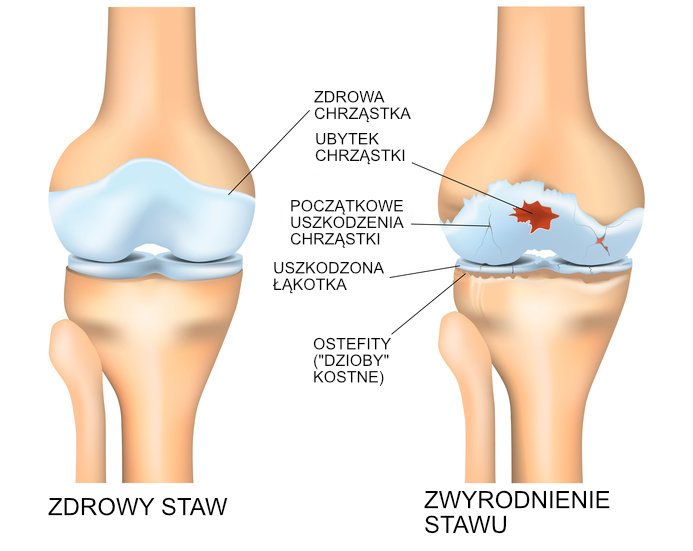

Zdrowy staw kolanowy składa się z dobrze do siebie pasujących powierzchni kości udowej, piszczelowej oraz rzepki. Powierzchnie te są gładkie i wyścielone warstwą ochronnej chrząstki, która pełni funkcję amortyzatora. Dzięki temu ruchy w stawie są płynne i bezbolesne. Powstające podczas użytkowania stawu niewielkie uszkodzenia są naprawiane przez organizm. Niestety, wraz z upływem lat zdolność do regeneracji maleje i uszkodzenia w stawie mogą stopniowo narastać. Chrząstka zużywa się, co sprawia, że powierzchnie stawowe trą o siebie podczas chodzenia powodując ból i sztywność kolana. Wokół stawu narastają też wyrośla kostne zwane osteofitami, które mogą dodatkowo utrudniać ruchy w kolanie oraz powodować ból.

- Deformacje stawów. Zdeformowany staw będzie zużywał się szybciej, podobnie jak opona na źle ustawionym kole samochodu. Dlatego też tak zwane krzywe, czyli koślawe lub szpotawe kolana ulegają degeneracji znacznie szybciej normalnie.